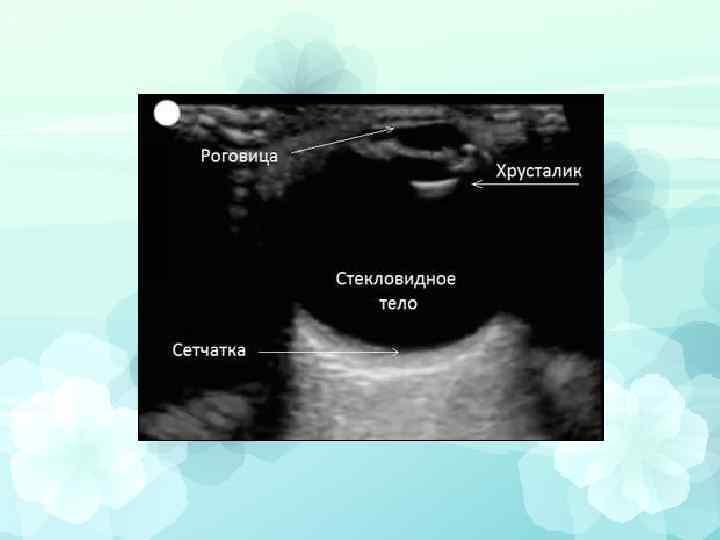

Ультразвуковое исследование Особенно информативно в следующих случаях: 1. Диагностика отслойки сетчатки 2. При поиске друз диска зрительного нерва 3. При обследовании внутриглазной опухоли

• А-метод (одномерная эхография). • В-метод (двухмерная эхография). • Комбинация А- и В-методов. • Ультразвуковая биомикроскопия. • Трехмерная эхография. • Энергетическая допплерография. • Импульсно-волновая допплерография. • Ультразвуковое дуплексное исследование.